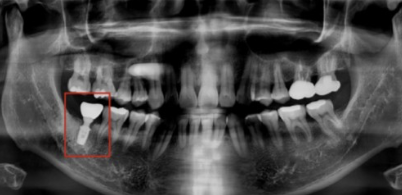

생각보다 금방 끝나고 원장님이 사진을 보여주시는데

저는 3번의 경우로 지대주에 금이 가서 음식물이 침투했고

그로인해 염증이 심한 상태였으며, 잇몸도 낮아진 상태였어요.

제가 거울로 봤을 때에는 염증이 작게 살짝 올라와있었는데, 열어서 보니까 안쪽에는 크게 튀어나와있었습니다.

외부로 보이는 것 보다 훨씬 심했던 것이죠.

(현재는 크라운과 지대주를 제거하고 염증치료 뒤 안쪽에 약을 채워넣고 왔는데

일단...엄청..욱신거리구요...염증이 심했던 터라 노란 고름이 조금씩 새어나오고 있을 정도입니다.)

임플란트 할 당시 썼던 크라운과 지대주는 이미 음식물로 코팅이 되어서

재사용한다고 해도 잇몸이 쉽게 차오르지 않는다고 하셨습니다.

지대주에 금이 간 이유는 제가 공간이 좁아서 조금 작은 나사로 했었는데,

아무래도 힘을 제대로 못받는 상태에서 충격에 의해 금이 간 것 같다며

염증이 가라앉는대로 다음주에는 인공치근도 제거하고,

염증 상황봐서 빠르면 인공치근 제거하는 당일, 늦으면 회복된 이후에

더 길이가 긴 인공치근을 잇몸뼈 깊숙이 박기로 했습니다.

인공치근을 새로 심고 3개월 뒤 잇몸 차오르는 걸 보고 지대주를 심고 크라운을 씌워야 합니다.

결국 인공치근, 지대주, 크라운 모두 1년 반도 채 사용하지 못하고 폐기하게 되었고,

또 수 개월에 걸친 임플란트 수술을 진행해야 하는 시작점에 돌아왔습니다.